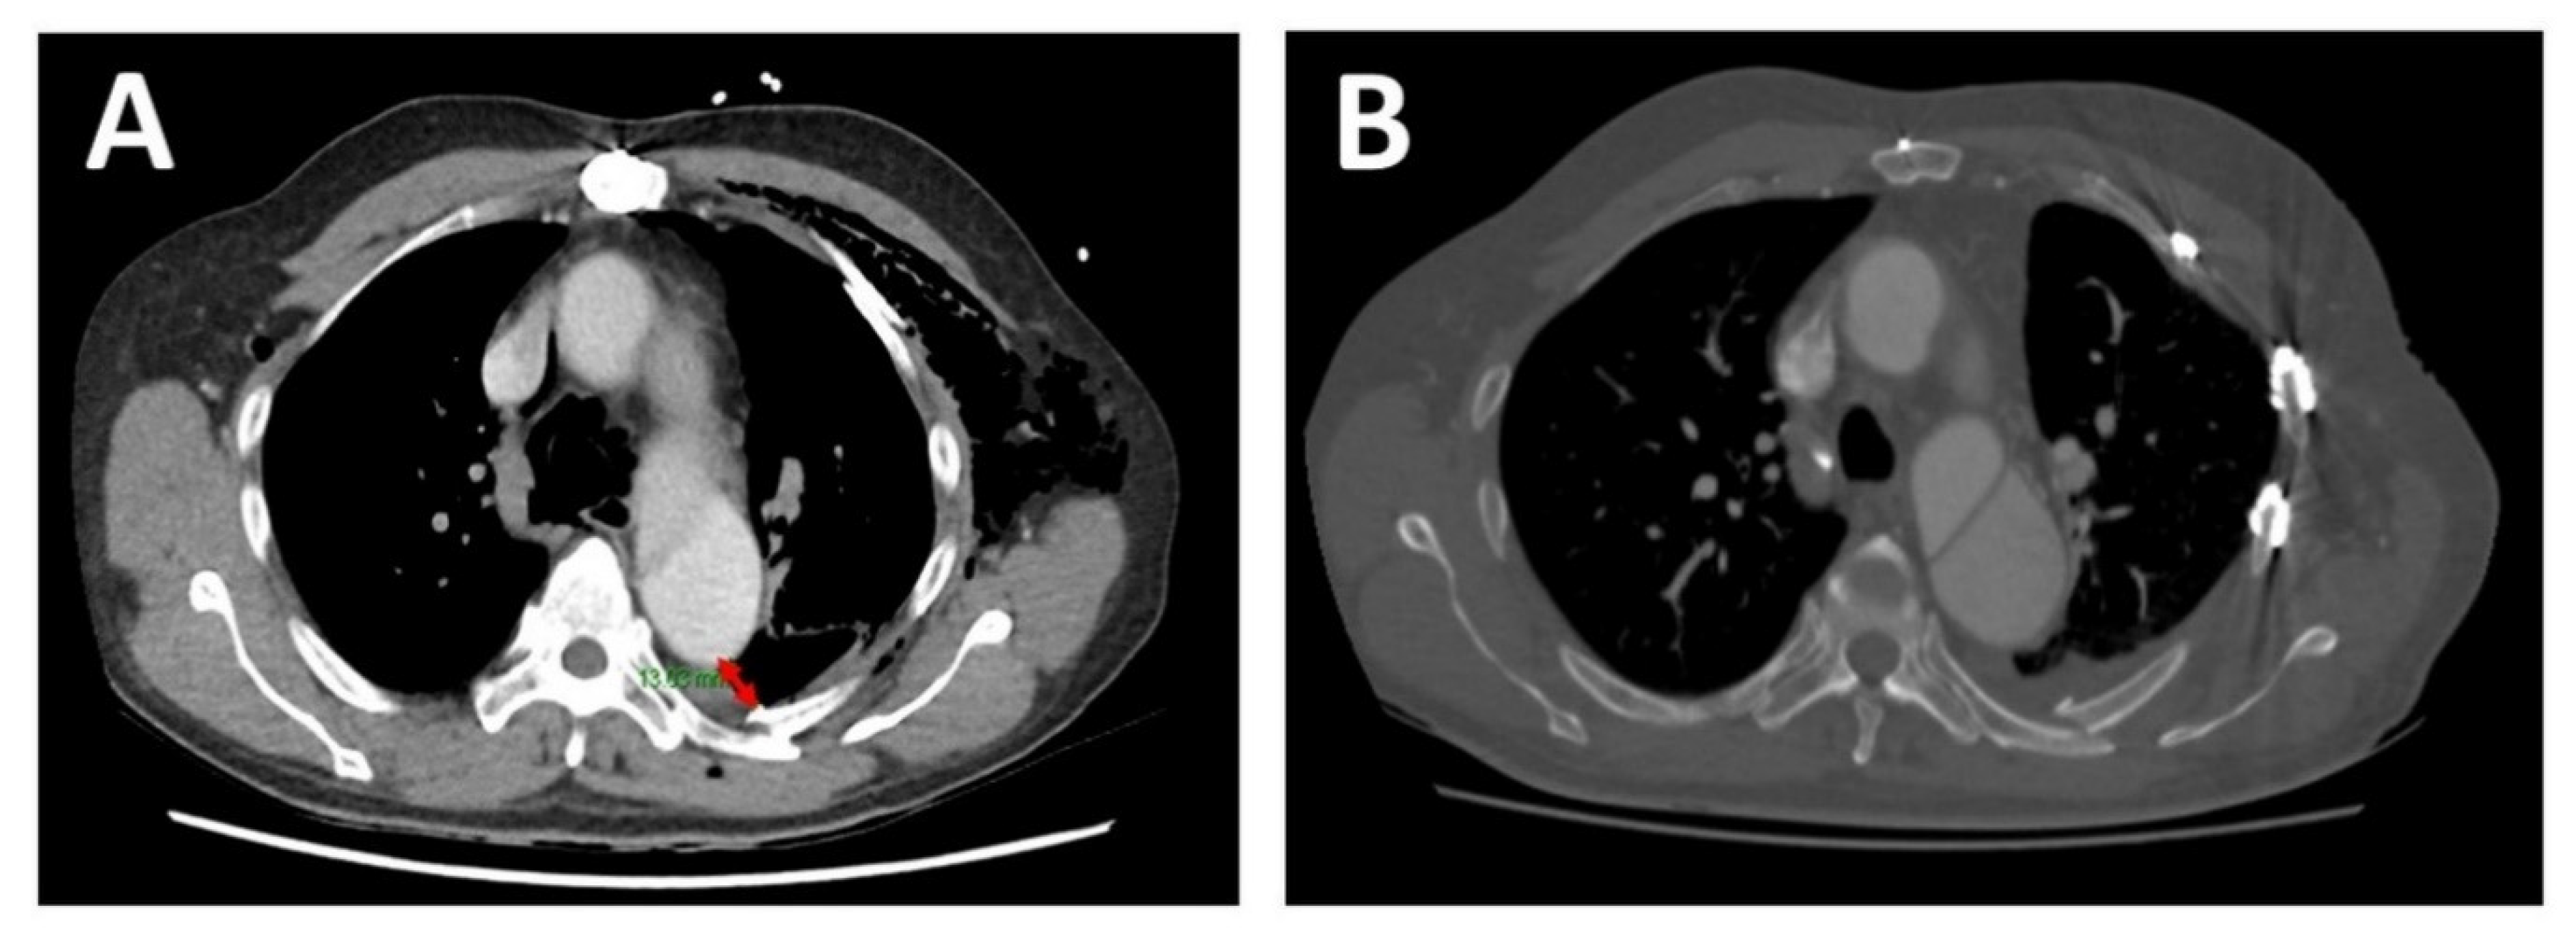

A 66-year-old man presented to the emergency department after being struck by a cyclist. He complained of left-sided chest, shoulder/hip pain, and post-traumatic amnesia. He had a past medical history of hypertension, hypercholesterolaemia, and chronic, residual, Stanford Type A AD, which was repaired in 2014. On examination, he was haemodynamically stable with a brachial blood pressure of 115/71 mmHg, no significant blood pressure differences between arms, a respiratory rate of 22 breaths per minute, and a pulse oximeter saturation of 95% on 2 litres nasal prong oxygen. He had a tender left chest wall posteriorly and laterally, with extensive subcutaneous emphysema over his chest wall and neck bilaterally. He had reduced air entry in his left chest. His had dual heart sounds without murmurs. A computed tomography (CT) scan of his chest showed a comminuted left clavicle fracture, left rib fractures from the second to the ninth, with flail segments from the third to the ninth, and a moderate left pneumothorax (Figure 1 and Figure 2). The sixth posterior rib fracture was only 13 mm away from the aorta (Figure 1 and Figure 3A). The CT also demonstrated that the residual AD had increased in size since the original diagnosis in 2014. A CT of his brain and facial bones showed no new intracranial pathologies or fractures.

After fixation, two 19 French intercostal catheters were inserted before closing. The thoracic wall muscles and subcutaneous fat were approximated with 2-0 Vicyrl and the skin was closed with subcuticular 3-0 Monocryl. The patient was monitored in the high dependence unit for 2 days with no complications. On day 7 of admission, the left clavicle was fixed with surgical plating. Functional lung expansion improved substantially (>50%) on day 8 of his admission, which corresponded to day 2 after SSRF. On day 10 of his admission, corresponding to day 4 after SSRF, he was able to perform incentive spirometry adequately (1200 mL). He was discharged on day 14 of his admission with no opioid analgesia and without supplemental oxygen. He was followed up in an outpatient clinic after 4 weeks, where his pain was demonstrably well controlled (0/10 at rest and 3/10 on exertion), and his chest X ray and chest CT revealed good expansion of his chests with plates and screws in situ (Figure 3B).

Figure 3. Chest CT (axial view)—preoperative and 6-week postoperative images. (A). Preoperative chest CT demonstrating the proximity of the sixth rib fracture site to the false lumen of the aorta (~13 mm as marked by the double-tipped red arrow). (B). 6-week postoperative chest CT showing in situ RibFixTM plates.